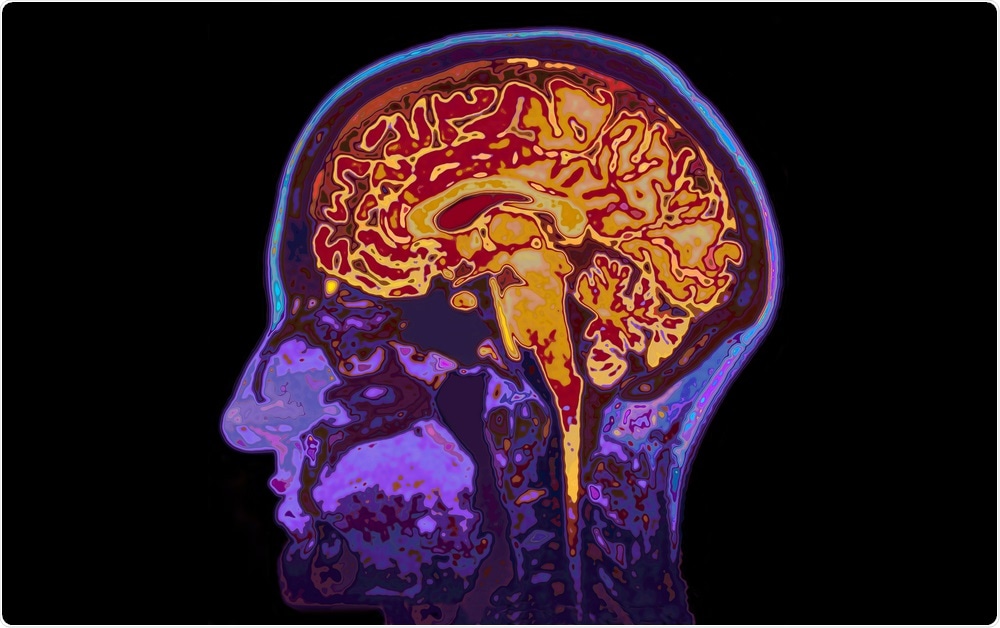

Concussion has been linked to long-term brain damage.SpeedKingz | Shutterstock